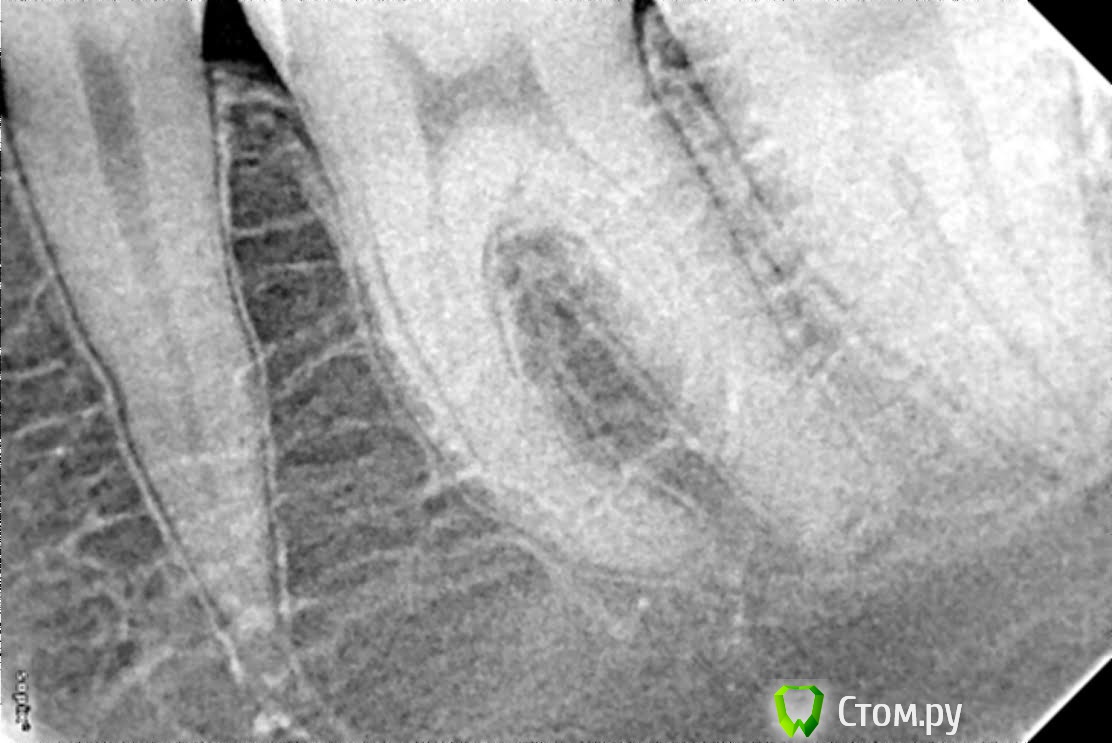

jackos Опубликовано 3 августа, 2014 Поделиться Опубликовано 3 августа, 2014 (изменено) Здравствуйте. Во время прорезывания 8 зуба распухла десна, затем воспаление перешло на десны 6-7 зуба.После посещения стоматолога сказали, что это выходит гной из 6 зуба и только удалять. Так ли это, обычным лечением уже ничего не сделать? До роста зуба мудрости зуб никак не беспокоил,лечил только от кариеса. Спасибо. Изменено 3 августа, 2014 пользователем jackos Ссылка на комментарий

red_butler Опубликовано 3 августа, 2014 Поделиться Опубликовано 3 августа, 2014 На снимке, проблем с 6 зубом не вижу, мудрый удаляйте 1 Ссылка на комментарий

Гарриевич Опубликовано 3 августа, 2014 Поделиться Опубликовано 3 августа, 2014 по снимку проблем с 6кой нет Ссылка на комментарий